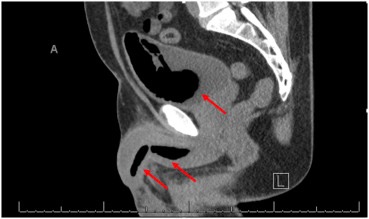

Рис. 1. Компьютерная томография: Стрелки указывают на монтажную пену в мочевыводящих путях.